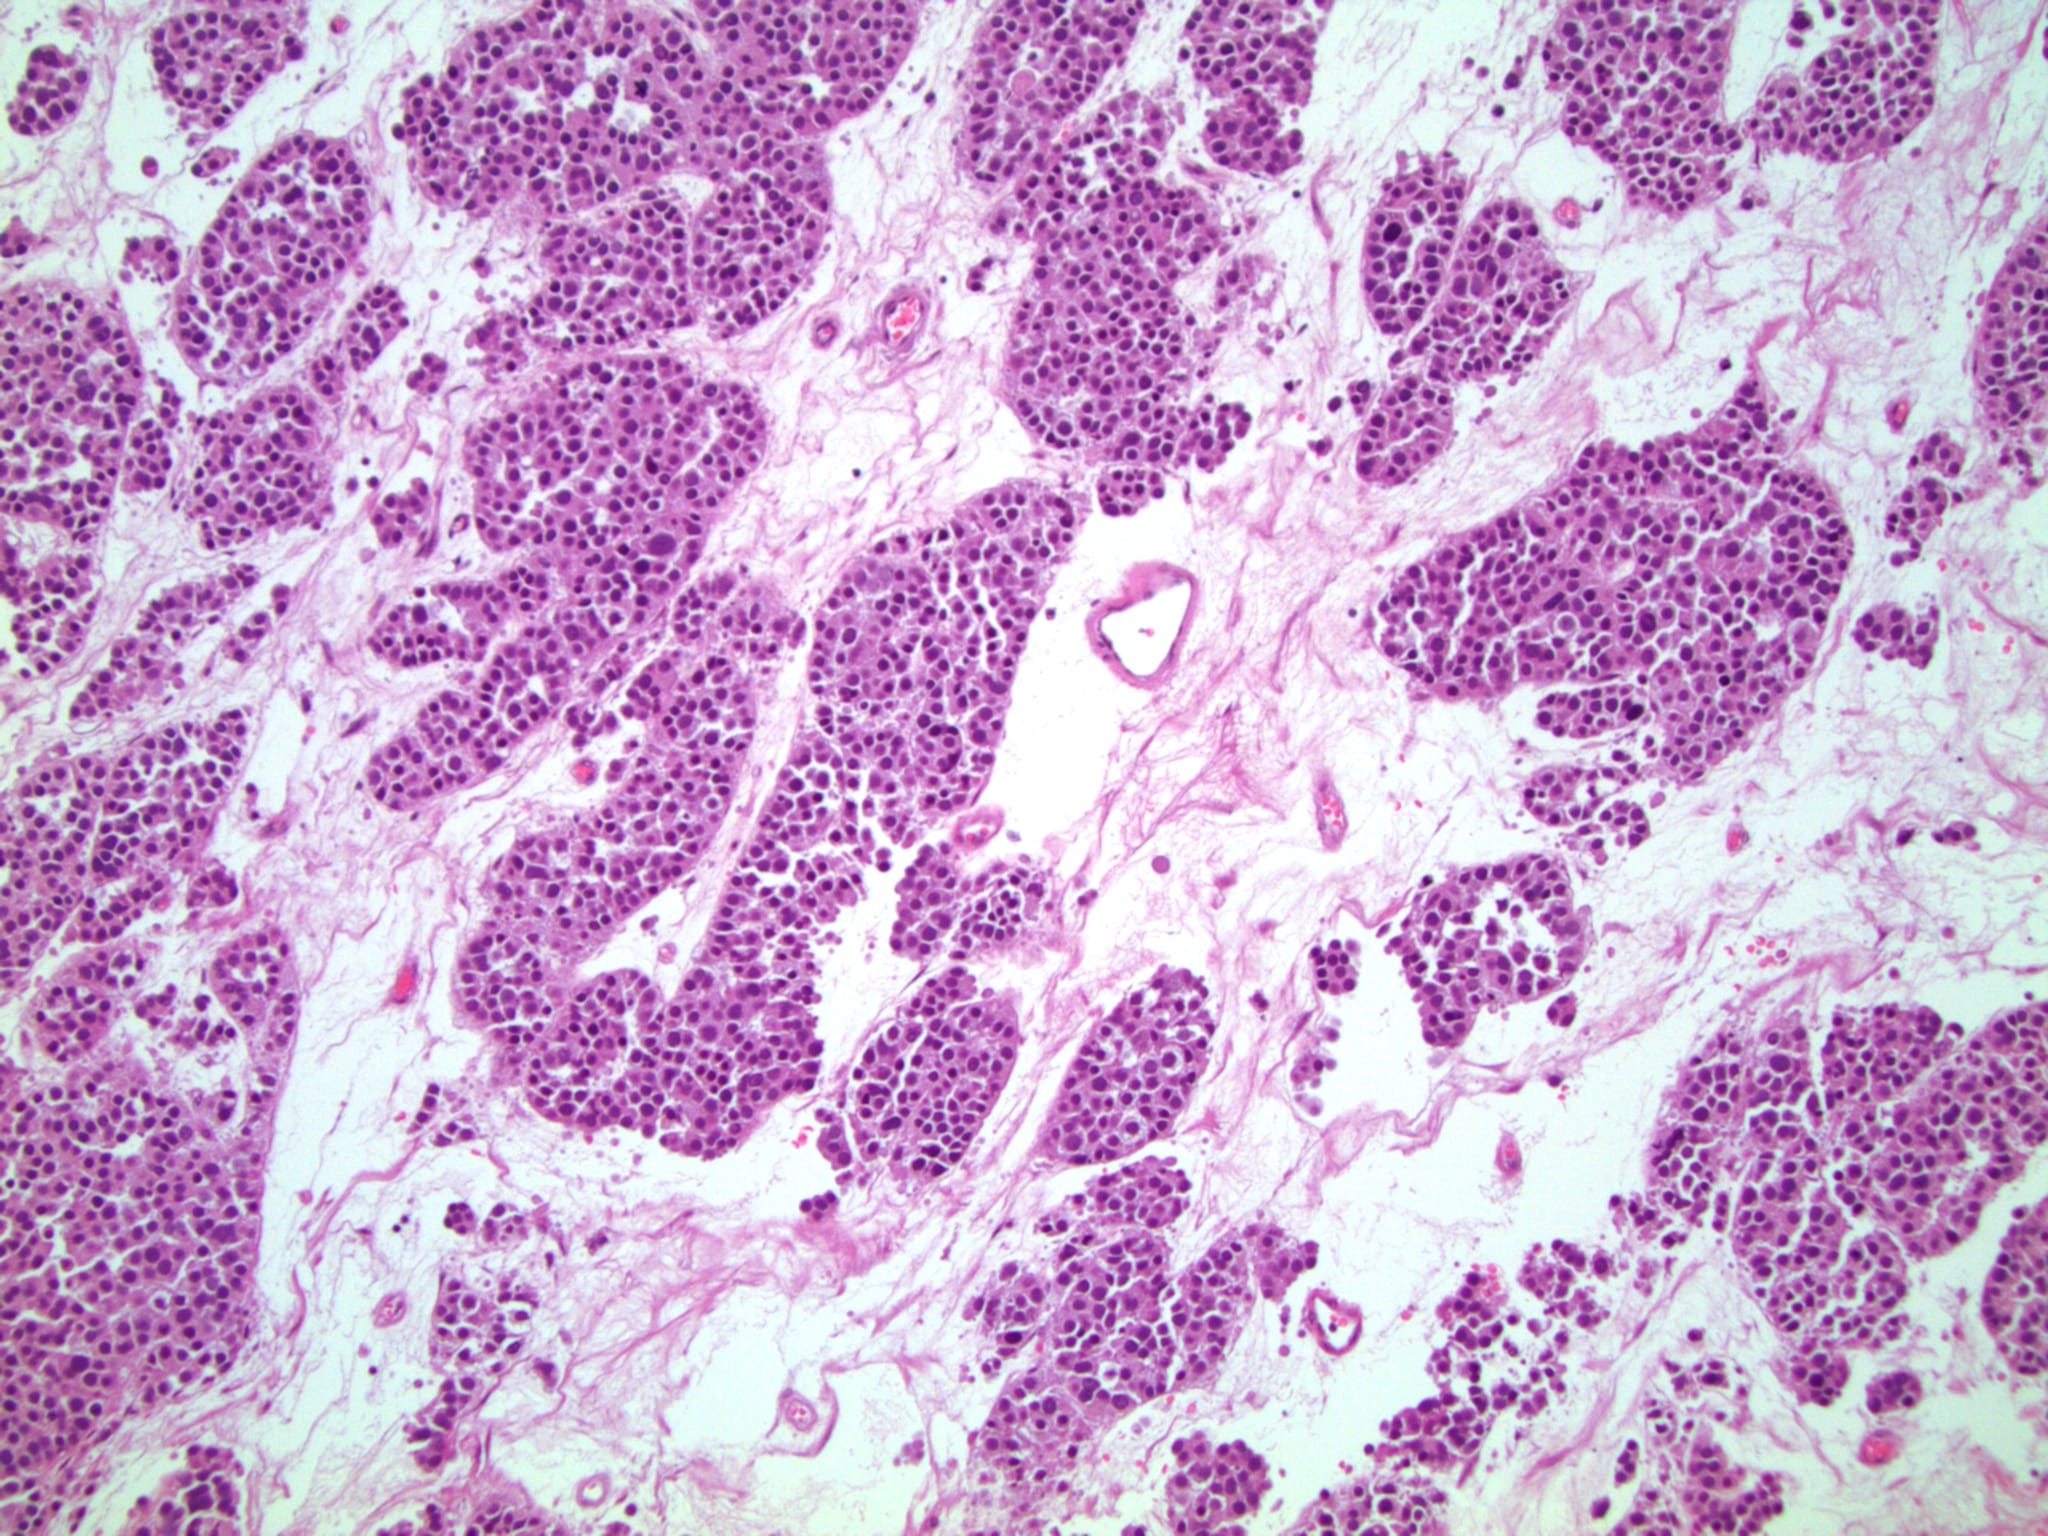

Патолоджи аутлайн

Патолоджи аутлайн 113 фото